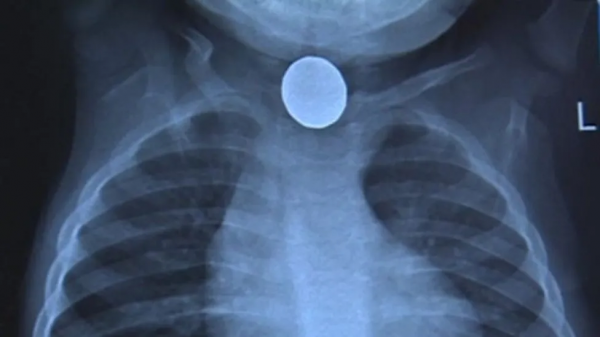

最後醫生終於發現了真正的病因——讓休伊生命垂危的竟然是一顆小小的紐扣電池,它死死地卡住在休伊的食道里。

而其產生的酸已經把小休伊的心臟燒出了一個硬幣大小的洞,醫生表示這個傷恐怕永遠不會恢復。